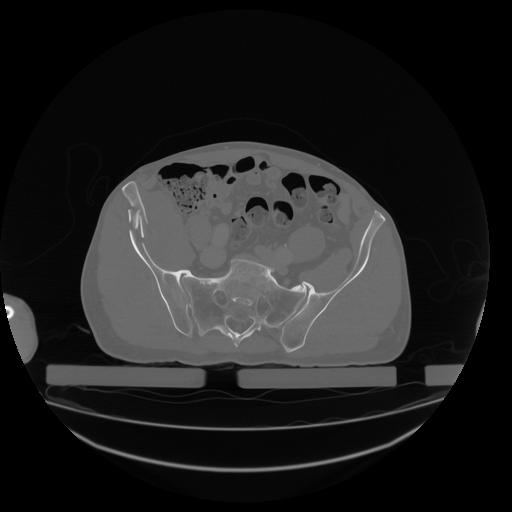

34 CUERPO,CE,Vol,1.0,CUERPO,,